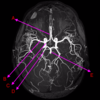

Which arteries do the arrows point to? [1]

Lenticulostiate arteries

Q